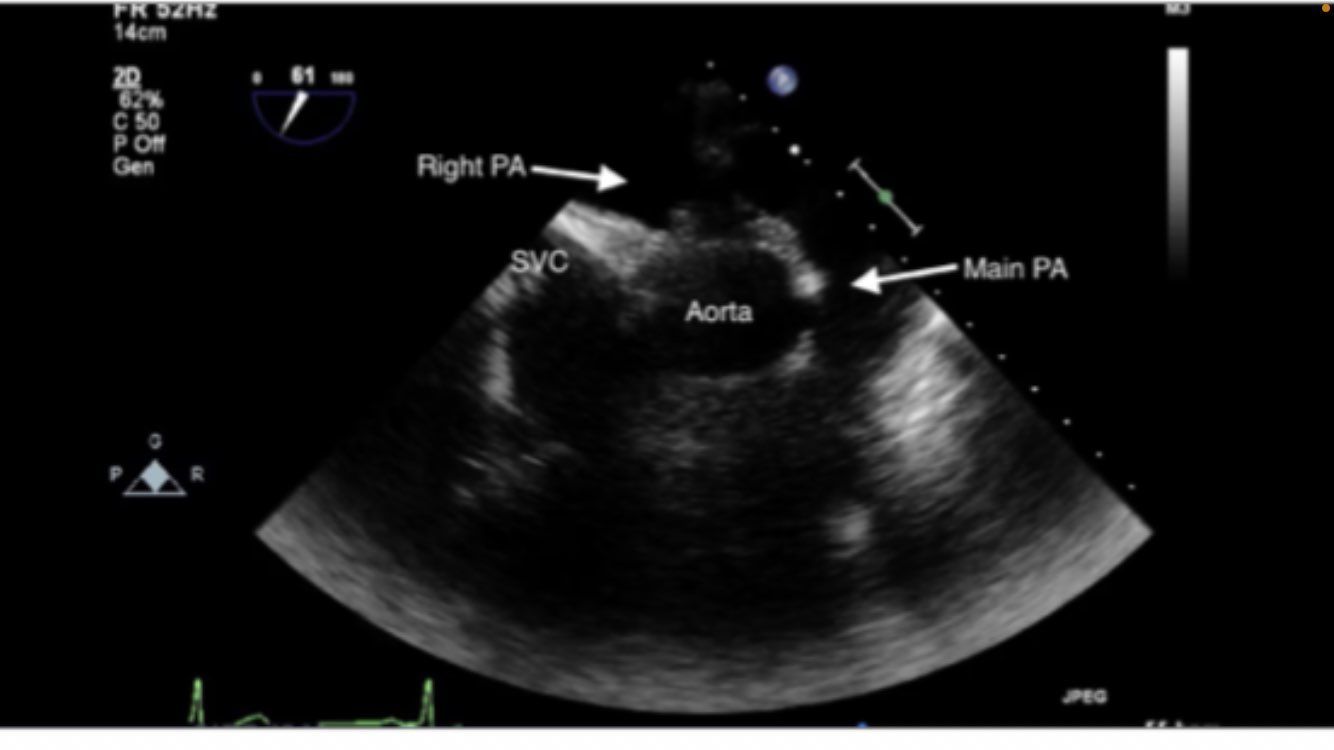

Mid esophageal RV inflow and outflow

TRICUSPID NOT MITRAL VALVE